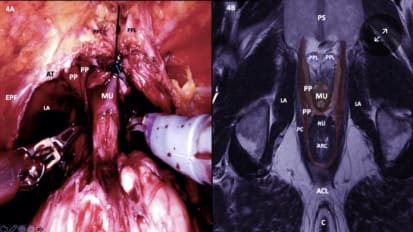

News A Pioneering Clinician and Researcher Produces Innovations in Nerve Sparing Techniques to Tailor a Unique Approach for Each Patient